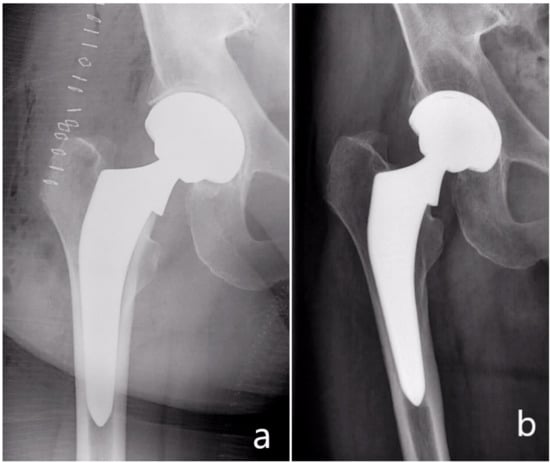

In five THA (4.2%), subsidence of the stem was observed: in four cases (3.4%) the subsidence was <5 mm and in one patient (0.8%) >5 mm. The last patient was a 78-year-old female patient with a BMI of 26 kg/m2 and a Dorr type B femoral bone structure who showed a >5 mm subsidence of the stem, whose collar reached the lesser trochanter then stopped. In all five cases the subsidence was detected at three months. At 12 months and five years there was no progression of the subsidence. All five patients had no clinical symptoms and showed an ingrown stem at the one-year and five-year follow-ups. None of the patients with subsidence presented relevant radiolucencies.

The subsidence frequency in this study was in total 4.2% (5 patients): 3.3% (4 patients) <5 mm and 0.8% (1 patient) >5 mm (Figure 5). The body mass index of these patients ranged from 26.4 to 27.2 kg/m2. In the postoperative radiographs, all five stems showed a neutral stem alignment and a collar to medial corticalis distance of <1 mm. The femoral neck-shaft angle in all five patients was in the normal range and varied from 129 to 134°. No fractures were detected. On the other hand, four of these five patients presented with a Dorr type B femur and one patient with a Dorr type C femur. Four of them were females. The mean age of the five patients was also 75 years higher than the total mean age of the whole collective (67.7 years). These factors, including poor bone quality, age, and femur geometry may have had a possible effect on the observed subsidence [40,41,42].

Further analysis of the illustrated case in Figure 5 shows that the subsidence occurred although the collar abuts the resection plane of the femoral neck. An explanation of the subsidence occurrence here is a possible preexisting fracture or a missed intraoperative fracture. This theory is supported by the altered cortical bone distal to the lesser trochanter. In addition, the cortical thickening medial to the tip of the stem may be a consequence of a distal force transmission, which may, in turn, suggest a non-functional collar.

Figure 5. (a) Postoperative radiograph, (b) radiograph of the same patient at three months showing subsidence of the stem.